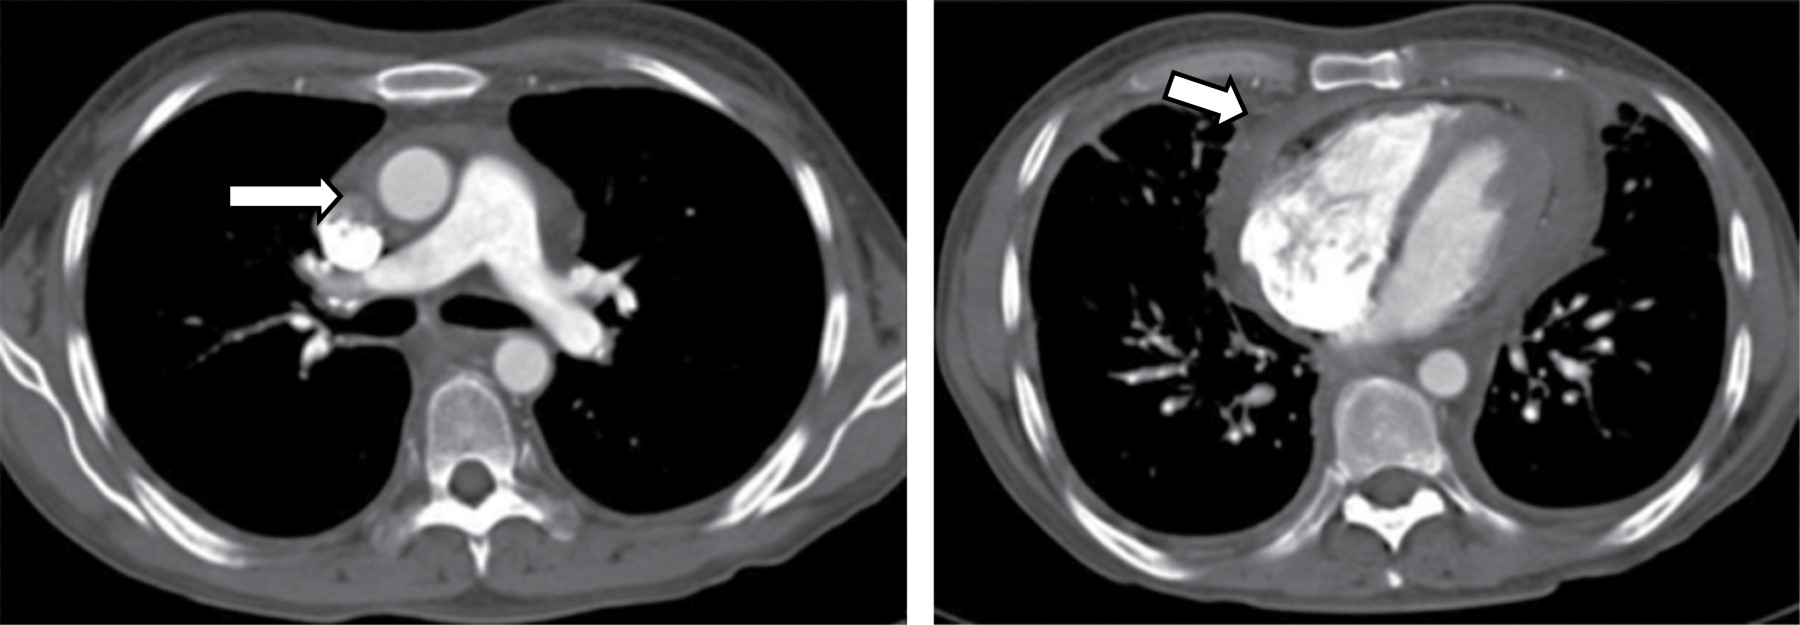

En la TC, típicamente se manifiesta como masas de atenuación de tejidos blandos que obliteran planos grasos mediastinales y encasilla o invade estructuras adyacentes. Sherrik y colaboradores8 identificaron dos patrones de invasión tomográfica: un patrón focal y un patrón difuso. El patrón focal (Figura 3) visto en 82% de los casos, se manifiesta como una masa con atenuación de tejidos blandos que con frecuencia calcifica (63%) y usualmente se localiza en las regiones paratraqueal derecha o subcarinal o en el hilio. El patrón difuso (Figura 4), visto en 18% de los casos como una masa infiltrante no calcificada que afecta múltiples compartimentos mediastinales. El patrón difuso ocurre en el estadio de otros desórdenes fibrosantes idiopáticos tales como fibrosis retroperitoneal.

El grado de realce es variable y es útil para describir encasillamiento u obstrucción de arterias pulmonares y venas. Reconstrucciones en dos o tres dimensiones pueden facilitar el abordaje quirúrgico o terapia local de estas lesiones.

La obstrucción venosa frecuentemente resulta en anormalidades parenquimatosa visible en la TC, tales como regiones focales o difusas de incremento de la atenuación parenquimatosa focal o difusa, atenuación en vidrio deslustrado, y engrosamiento septal interlobular.